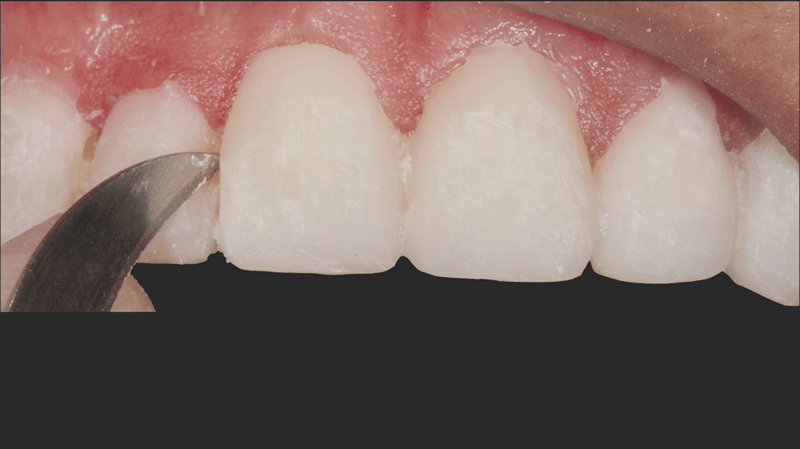

- Veneerseparatie: Met een mesje #12 en een separeerzaag werden de veneers vervolgens zorgvuldig van elkaar gescheiden, voor een preciezere afwerking.

- Prepareren van de sulcus: Er werd een gebreide Ultrapak™-draad maat 0 in de sulcus aangebracht ter voorbereiding op het etsen.

- Etsen van onbeslepen glazuur: Er werd 30 seconden geëtst op het onbeslepen glazuur. Hiervoor werd Ultra-Etch met 35% fosforzuur gebruikt.